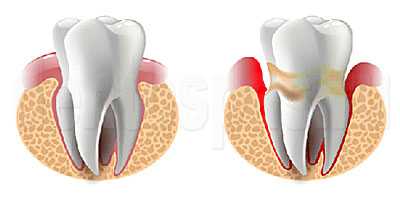

В некоторых случаях причиной удаления зуба служит периодонтит.

Периодонтит развивается как осложнение кариеса, когда в случае отсутствия должного лечения или некачественного лечения нерв в зубе погибает, и воспалительный процесс через каналы зуба выходит за его пределы в костную прилегающую ткань.

При хроническом периодонтите в тканях периодонта развивается очаг воспаления. Он может формироваться долго, несколько лет, оставаясь незаметным — без повышения чувствительности, болезненных ощущений, реакции на температурные раздражители, надавливание и т.п. В других случаях воспаление протекает остро: коронка становится болезненной, десна краснеет и опухает, на ней формируется свищ. Периодонтит опасен постепенным изменением структуры окружающих зуб тканей:

- разрушаются связки, которые удерживают зуб в лунке;

- рассасывается образованная альвеолярными отростками кортикальная пластинка;

- начинается деструкция костной ткани.

Периодонтит — это заболевание, вызванное бактериями, травмой или лекарственными препаратами, в результате которого происходит воспаление комплекса соединительной ткани (периодонта), расположенной между цементом зуба и зубной альвеолой. [9] [20]